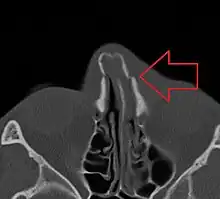

Nasal bone fracture -

Bilateral nasal fracture as seen on CT scan

The most common causes include assault, trauma during sports, falls, and motor vehicle collisions.[1] Diagnosis is typically based on the signs and symptoms; with plain X-ray rarely of benefit.[1][6] CT scan may be useful if concerns of other fractures or complications are present.[6][4]

Nasal fractures are usually identified visually and through physical examination.[1] Medical imaging is generally not recommended.[1][2] A priority is to distinguish simple fractures limited to the nasal bones (Type 1) from fractures that also involve other facial bones and/or the nasal septum (Types 2 and 3). In simple Type 1 fractures X-Rays supply surprisingly little information beyond clinical examination. However, diagnosis may be confirmed with X-rays or CT scans, and these are required if other facial injuries are suspected.[2]